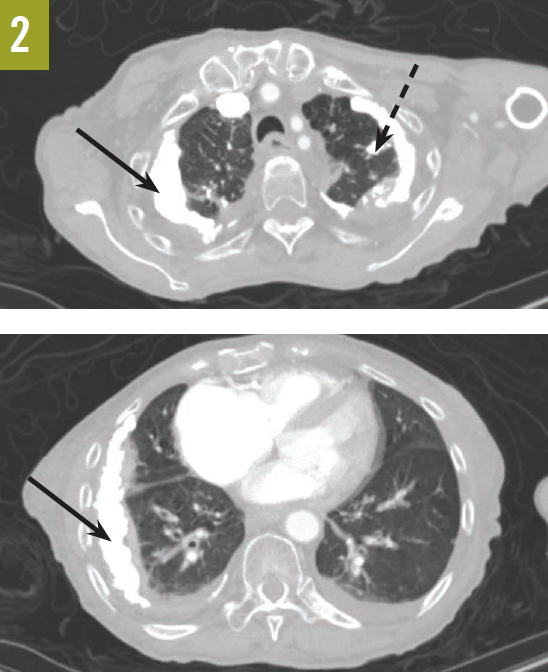

Upon admission, a chest radiograph revealed hyperlucency of the right hemithorax with a right basilar infiltrate (Figure 1). Computed tomography (CT) of the chest showed extensive unilateral bullous emphysema involving the entire right lung from apex to base (Figure 2). The emphysema was confined to one side and was so severe and voluminous that the mediastinum was pushed far away from its midline alignment with the sternum into the left hemithorax, resulting in compression and atelectasis of the left lung. There was also a right-sided pneumonia superimposed on the background of emphysema.

Figure 1. A chest radiograph showed hyperlucency of the right hemithorax and a right basilar infiltrate.

Figure 2. A CT scan of the chest at the level of the carina showed severe and voluminous bullous emphysema of the right lung; the mediastinum is pushed far away from its midline alignment with the sternum into the left hemithorax, and a right basal pneumonia is present.